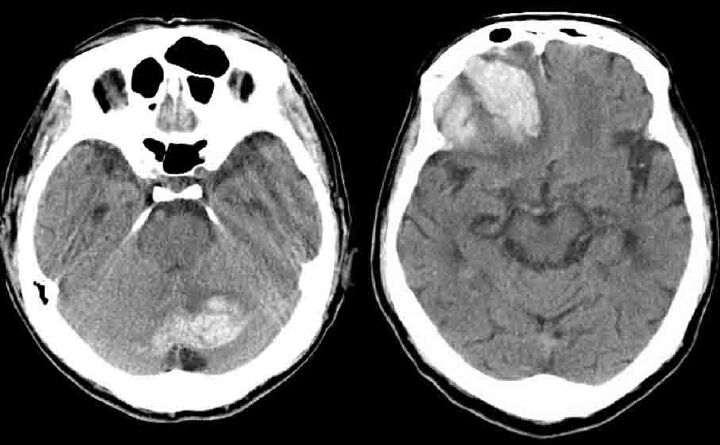

【この動画怖い】ゲーム配信者(32)が発症!脳梗塞の瞬間…突然しゃべれなくなり 2024年9月29日 最終更新日時 : 2024年9月29日 ぐはっアンテナ 八木勇征の魅力を徹底解剖!彼の成長と影響 【芸能】堺正章が語る 人気ドラマ『西遊記』打ち切りの真相 「天竺に着く前に終わった…」 【LDH】三代目JSB今市隆二メンバー 活動自粛・・・ 【画像】井口裕香さん(37)、まだまだ全然イケるwwwwwwwwwwwwwwwwwwwwwwwwwwwwwwwww ジャングリア沖縄がここまで叩かれている理由がわかったwwwwwwwwww 【苦悩】奥菜恵「自分では清純派とも魔性とも思っていなかった」 【画像】吉岡里帆、理想の男性は「京都の人より九州男児が好き」 【画像】広末涼子さん(45)の近影 【画像】ジャングリア沖縄🌿🦖、ファンもアンチも黙らせてしまう 元坂道?アイドルがデビュー 【この動画怖い】ゲーム配信者(32)が発症!脳梗塞の瞬間…突然しゃべれなくなり 脳梗塞 NIND-IIIの分類では局所性脳機能障害をTIAと脳卒中に分類する。脳卒中は脳出血、くも膜下出血、脳動静脈奇形に伴う頭蓋内出血、脳梗塞に分類し、脳梗塞はアテローム血栓性脳梗塞・心原性脳塞栓・ラクナ梗塞・その他の脳梗塞の4種類に分類される。分類によって急性期治療および再発予… 144キロバイト (21,703 語) - 2024年7月5日 (金) 20:38 (出典 www.toyoko-stroke.com) 【放送事故】ゲーム配信中に脳梗塞になり話せなくなる【カジテツ玉子】 - YouTube(出典 Youtube) (出典 配信中に脳梗塞発症する動画をYouTubeで見たんだけど怖すぎだろ) 1 以下、5ちゃんねるからVIPがお送りします :2024/09/28(土) 10:42:05.039 ID:nwX4v8h70 急に来るんだな (出典 配信中に脳梗塞発症する動画をYouTubeで見たんだけど怖すぎだろ) 続きを読む 続きを見る 八木勇征の魅力を徹底解剖!彼の成長と影響 【芸能】堺正章が語る 人気ドラマ『西遊記』打ち切りの真相 「天竺に着く前に終わった…」 【LDH】三代目JSB今市隆二メンバー 活動自粛・・・ 【画像】井口裕香さん(37)、まだまだ全然イケるwwwwwwwwwwwwwwwwwwwwwwwwwwwwwwwww ジャングリア沖縄がここまで叩かれている理由がわかったwwwwwwwwww 【苦悩】奥菜恵「自分では清純派とも魔性とも思っていなかった」 【画像】吉岡里帆、理想の男性は「京都の人より九州男児が好き」 【画像】広末涼子さん(45)の近影 関連記事 関連記事はありません。